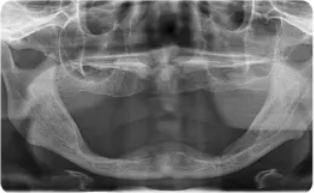

?种植牙前后口内数字化影像 , 左侧为种牙前 , 右侧为种牙后 。

文章图片

到院后 , 魏阿姨进行了口腔全景片以及CBCT等全方位口腔检查 , 检查结果显示魏阿姨口内牙齿全部缺失 , 牙槽骨萎缩 , 骨量不足 , 修复难度非常大 。